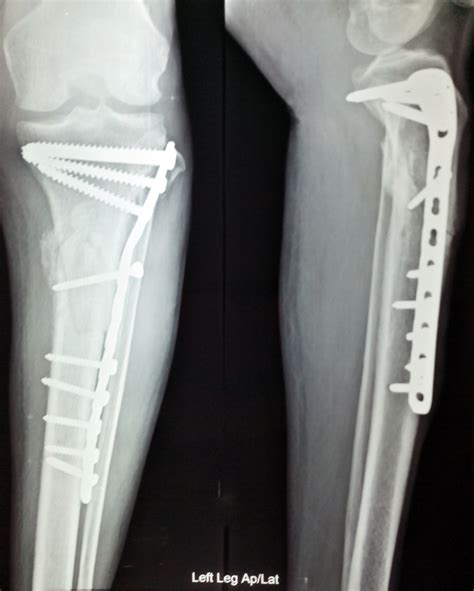

Doctors Explain Why A Fractured Shinbone Requires Surgery

Shinbone Fracture Treatment Method - HealthBeauty123 | Your Health ...